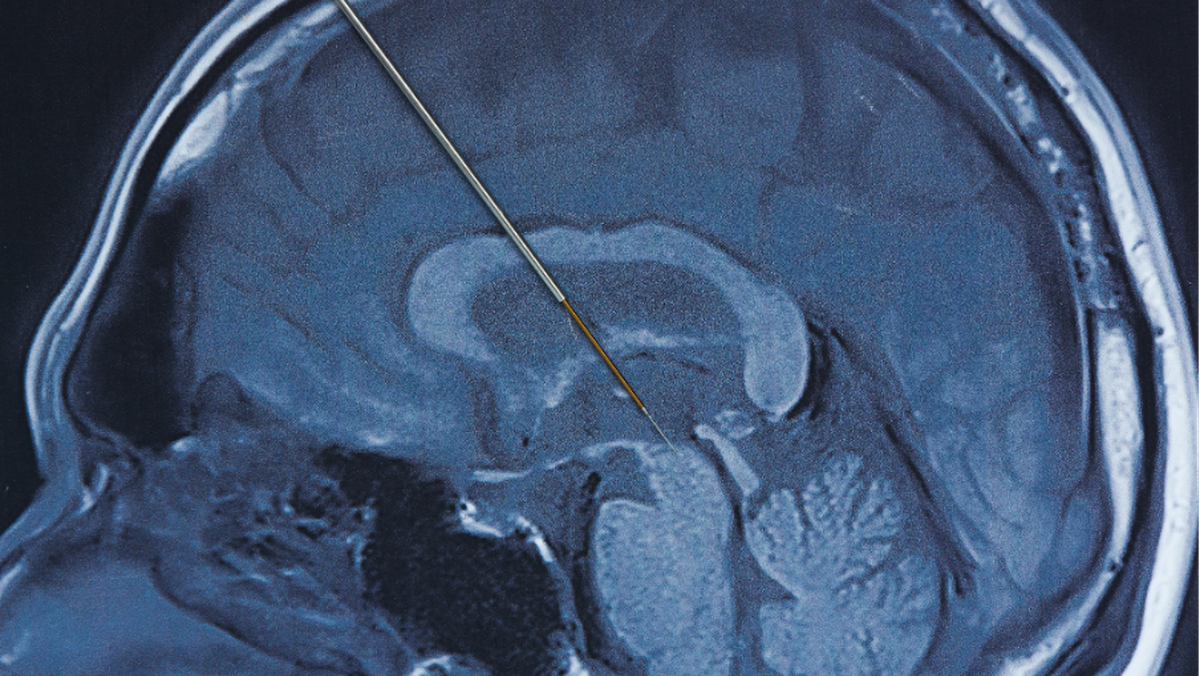

Deep brain stimulation merupakan prosedur bedah saraf yang melibatkan pemasangan elektroda Di area tertentu otak Untuk Memberi rangsangan listrik terkontrol. Stimulasi ini bertujuan mengatur kembali sinyal saraf yang terganggu akibat Penyakit Parkinson.

Ahli Kebugaran spesialis saraf Di Siloam Hospitals Kebon Jeruk, dr. Frandy Susatia, Sp.S, RVT, menjelaskan bahwa elektroda tipis ditanam Di otak dan dihubungkan Di Gadget stimulasi menyerupai alat pacu jantung. Gadget ini dipasang Di bawah kulit dada Pada atas dan bekerja secara terus-menerus mengirimkan impuls listrik sesuai pengaturan Ahli Kebugaran.

Tahap pertama adalah pemasangan elektroda Di otak Bersama bius lokal agar pasien tetap sadar. Di tahap ini, Ahli Kebugaran dapat Menimbang ketepatan lokasi elektroda Melewati simulasi yang diberikan, sambil pasien diminta Untuk Memberi umpan balik Yang Terkait Bersama perubahan Tanda-Tanda yang dirasakan. Setelahnya lokasi dan jumlah stimulasi yang optimal ditemukan, proses pemasangan Gadget DBS secara permanen Akansegera dilakukan.

Tahap kedua dilakukan Bersama bius umum Untuk menanam Gadget stimulasi permanen Di bawah kulit dada Pada atas. Elektroda Di otak Lalu dihubungkan Di Gadget tersebut Melewati kabel halus yang dipasang Di bawah kulit.